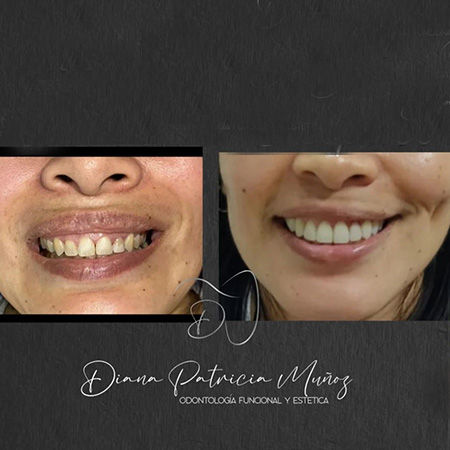

I am Dr. Diana Patricia Muñoz, a dentist in Cali specializing in comprehensive dentistry and oral rehabilitation. My passion is transforming smiles using cutting-edge techniques in cosmetic dentistry and orofacial harmonization, always with a focus on health, cosmetic, and functionality.

In my practice, I offer general and cosmetic dentistry, endodontics, periodontics, orthodontics, oral rehabilitation, smile design, and management of temporomandibular disorders such as bruxism, among other treatments. My commitment is to provide each patient with a personalized and comprehensive ca…

Before and After Gallery